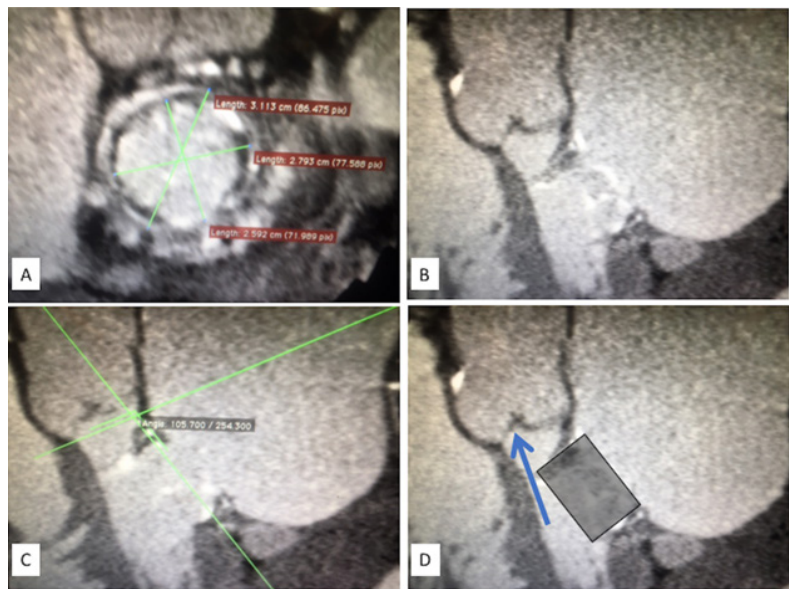

Percutaneous Transseptal Bioprosthetic Implantation in Failed Prosthetic Surgical Mitral Valve – Brazilian Multicenter Experience

Patients with surgical bioprosthetic dysfunction submitted to transseptal-TMVIV in 12 Brazilian hospitals were included. The significance level adopted was p<0.05.

From June/2016 to February/2019, 17 patients underwent transseptal-TMVIV. Their median age was 77 years (IQR,70-82) and median Society of Thoracic Surgeons predicted risk of mortality (STS-PROM) score was 8.7% (IQR,7.2-17.8). All patients had limiting symptoms of heart failure (FC≥III) and 5 (29.4%) had undergone more than one previous thoracotomy. Transseptal-TMVIV was successful in all patients. Echocardiographic assessment showed a significant reduction in mean mitral valve gradient (pre-intervention, 12±3.8 mmHg; post-intervention, 5.3±2.6 mmHg; p<0.001), in addition to an increase in mitral valve area (pre-intervention, 1.06±0.59 cm2; post-intervention, 2.18±0.36 cm2; p<0.001) sustained for 30 days. There was a significant and immediate reduction in the pulmonary artery systolic pressure, with an additional reduction in 30 days (pre-intervention, 68.9±16.4 mmHg; post-intervention, 57.7±16.5 mmHg; 30 days, 50.9±18.7 mmHg; p<0.001). During follow-up (median, 162 days; IQR, 102-411), significant clinical improvement (FC≤II) was observed in 87.5% of the patients. One patient (5.9%) had left ventricular outflow tract (LVOT) obstruction and died right after the procedure, and another died at 161 days of follow-up.

The first Brazilian experience with transseptal-TMVIV shows the safety and effectivity of the new technique. The LVOT obstruction is a potentially fatal complication, reinforcing the importance of patients’ selection and of procedural planning. (Arq Bras Cardiol. 2020; 115(3):515-524)